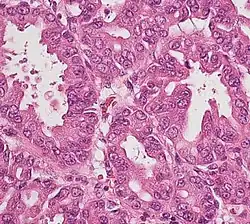

Micrographs of normal pancreas, pancreatic intraepithelial neoplasia (precursors to pancreatic carcinoma) and pancreatic carcinoma, H&E stain

Exocrine cancers are thought to arise from several types of precancerous lesions within the pancreas, but these lesions do not always progress to cancer, and the increased numbers detected as a byproduct of the increasing use of CT scans for other reasons are not all treated.[3] Apart from pancreatic serous cystadenomas, which are almost always benign, four types of precancerous lesion are recognized.

The first is pancreatic intraepithelial neoplasia (PanIN). These lesions are microscopic abnormalities in the pancreas and are often found in autopsies of people with no diagnosed cancer. These lesions may progress from low to high grade and then to a tumor. More than 90% of cases at all grades carry a faulty KRAS gene, while in grades 2 and 3, damage to three further genes – CDKN2A (p16), p53, and SMAD4 – are increasingly often found.[2]